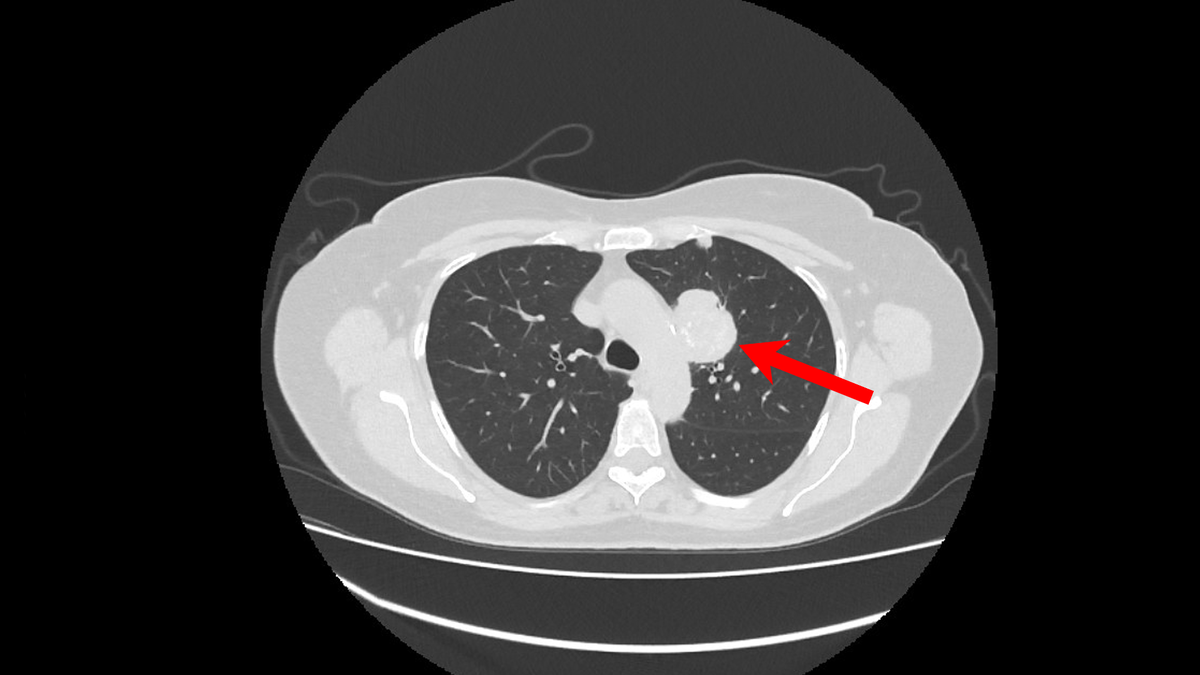

Развивается из железистых клеток, вырабатывающих слизь. Она чаще возникает в периферических отделах легкого, дальше от центра. Это самый распространенный тип рака легкого в целом. Хотя курение — главный фактор риска, аденокарцинома нередко встречается у некурящих людей, особенно у женщин. По характеру она может расти относительно медленнее других типов, но склонна к метастазированию в головной мозг, кости, печень и надпочечники.

Главная особенность лечения аденокарциномы — обязательный молекулярно-генетический тест опухоли. У многих пациентов, особенно некурящих, обнаруживаются специфические мутации в генах (EGFR, ALK, ROS1, BRAF и др.). Для таких мутаций существуют таргетные препараты в виде таблеток, которые могут очень эффективно контролировать болезнь с минимальными побочными эффектами. Хирургия остается основным методом на ранних стадиях. Лучевая терапия применяется как радикальное лечение при невозможности операции, после операции или для лечения метастазов. Химиотерапия используется на разных этапах, часто в комбинации с иммунотерапией, эффективность которой зависит от уровня белка PD-L1 в опухоли.